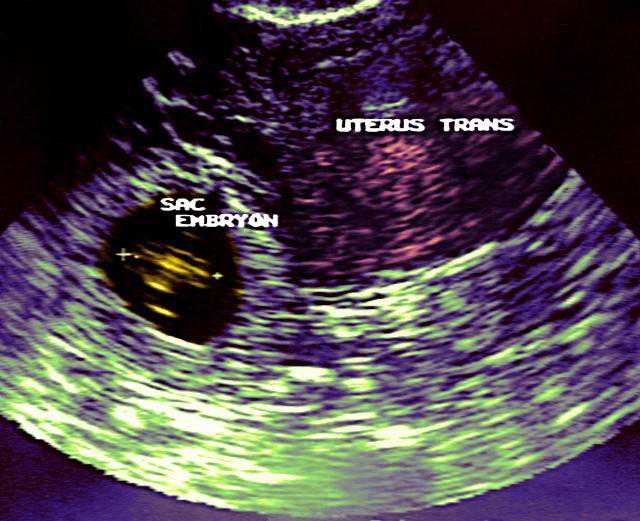

宫外孕B超

如果是孕囊在子宫内呢,那么我们就要根据孕囊的情况首先估算孕周,其次是孕囊内是否有胚芽,胚胎是否存活,也就是有没有心跳,还有孕囊和胚胎的数目,如果是多胎妊娠,还要区分羊膜囊和绒毛膜数(也就是是否有共用胎盘的情况),有没有子宫肌瘤等。除此之外,双侧附件区的情况也是要通过超声检查了解到的。

早孕